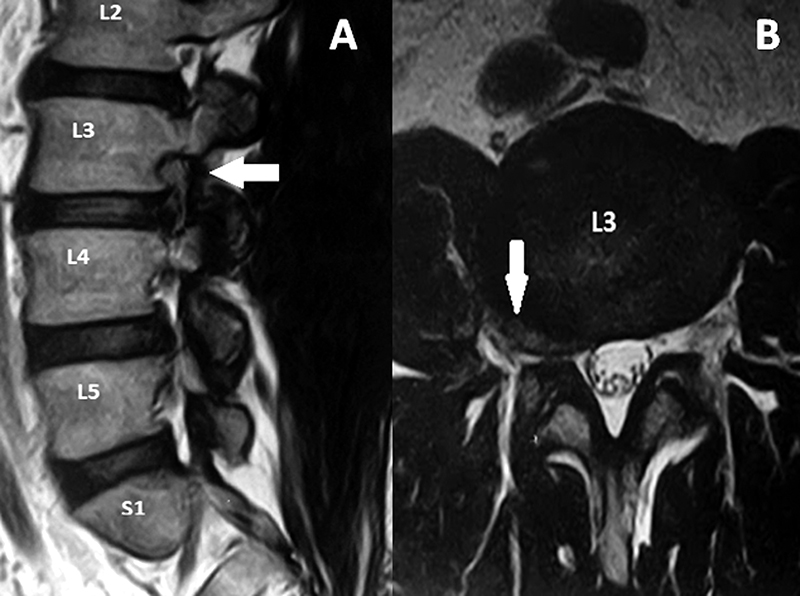

El tubo debe dirigirse al espacio intertransverso del disco a tratar, teniendo como límites del espacio de trabajo, las apófisis transversas a nivel superior e inferior y las apófisis articulares medialmente. Esto se corrobora realizando radioscopia con incidencia anteroposterior y perfil (fig. 1).

Figura 1: Radioscopía intraoperatoria. Colocación del sistema tubular mínimamente invasivo.